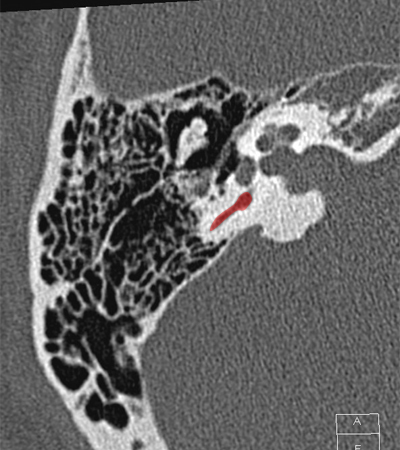

Cochlea Internal auditory canal Vestibule Posterior semicircular canal Head of malleus Body of incus Incudomallear joint